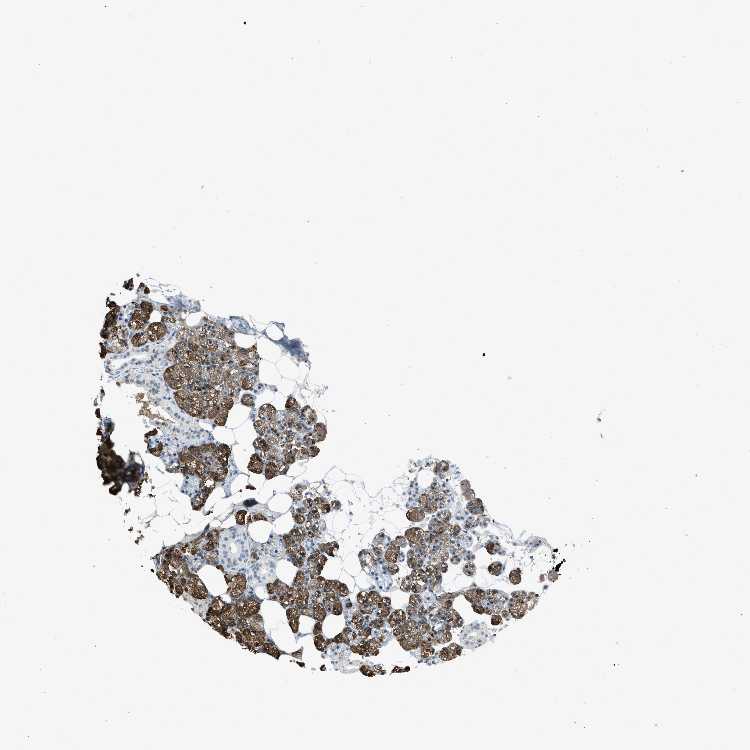

Antibody HPA016812

Glandular cells Low